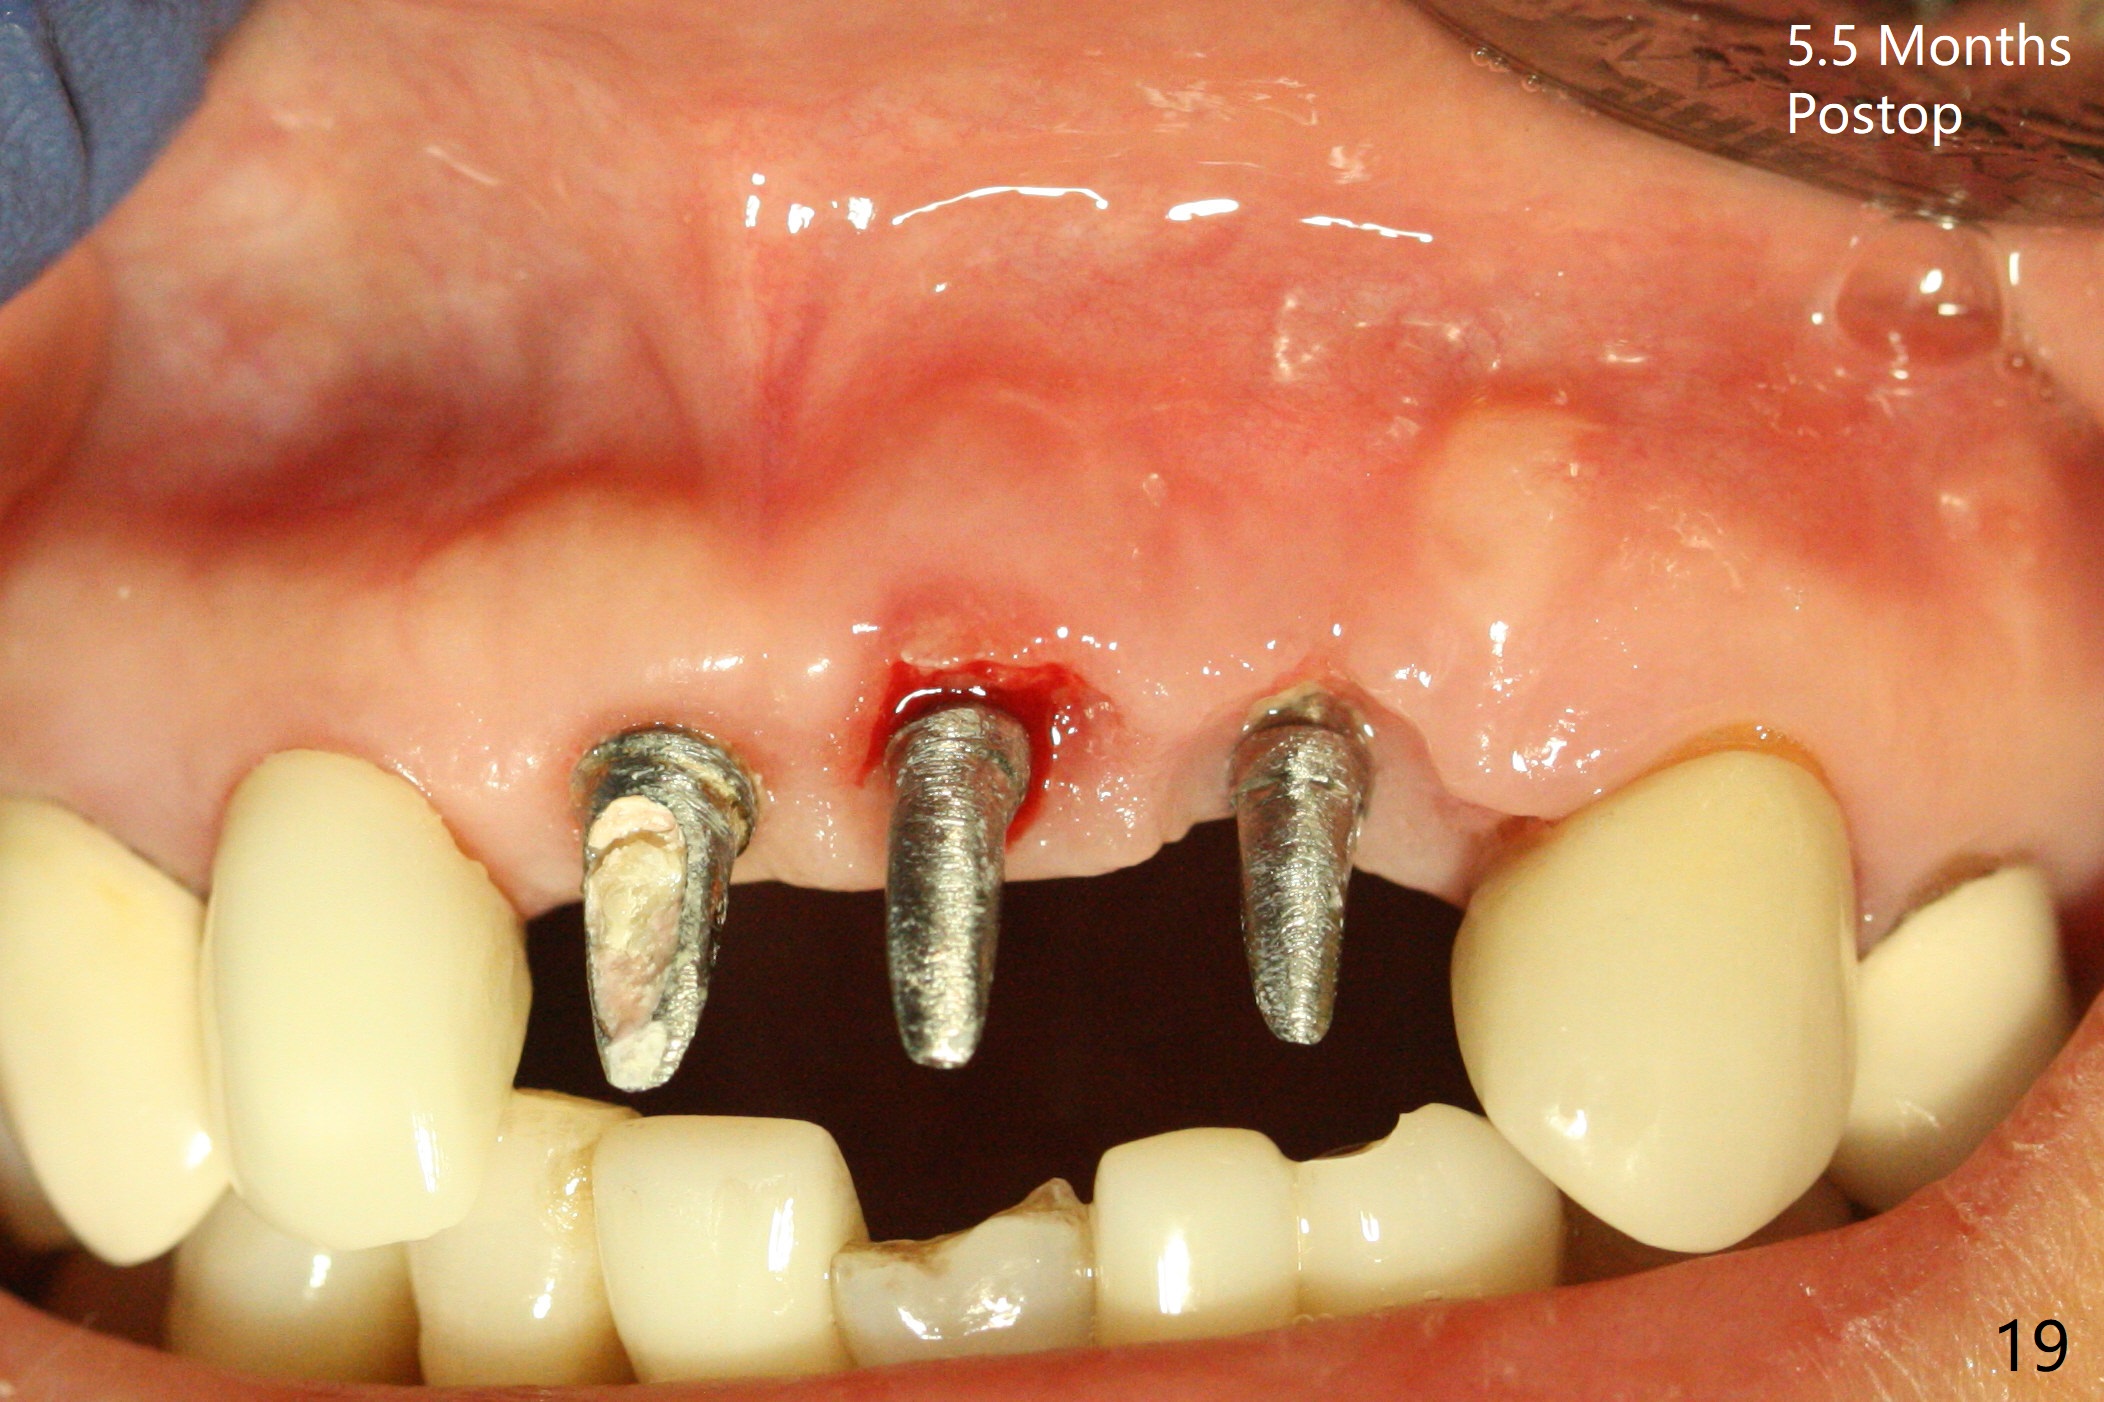

M

Incision shows exposure of microthreads at #9 and major threads at #10 due to buccal placement (Fig.1). There is bone palatal to the implant at #10 (Fig.2 P), to which a new implant will move. After implant removal, a narrower 1-piece implant (2.5x14(4) mm) is placed palatally at #10 (Fig.3,4) in combination of guide and free hand. At the site of #9 after implant removal, the guide is not used; a 3x17 mm angled 1-piece implant is placed with bad trajectory (Fig.5,6). After re-adjustment (Fig.7), the implant is placed at the right orientation (Fig.8). It appears that the guide is helpful. Allograft is placed mainly buccally (Fig.9,10 *), followed by a piece of collagen membrane (Fig.11). After tension release, flaps are approximated (Fig.12). The buccal gingiva at #9 and 10 recede nearly 2 months postop (Fig.13). Less recession at #9 is associated with more inflammation (Fig.14). The margin of the provisional is adjusted for gingival margin down growth and easy self cleaning with Water Pik (Fig.15). One month later, the gingival inflammation reduces, while there is no obvious buccal collapse (Fig.16,17). Impression is taken after laser gingivectomy nearly 4 months postop (Fig.18). While the gingiva around the implant at #9 is inflamed (periimplantitis?), the gingival cuff at #10 is well formed 5.5 months postop immediately before cementation (Fig.19). The buccal concavity at #10 is minimal (Fig.20). The gingival inflammation at #9 will be hopefully resolved after cementation of the final restorations (Fig.21). There appears to be new bone formation around the coronal implant threads 5.5 months postop (immediately post cementation, Fig.22). The microthreads at #9 may be not covered by the bone, the reason for the gingival erythema. The redness at #10 is asymptomatic 5.5 months post cementation (Fig.23). 粘固后两年牙槽嵴骨质并没有再生(图二十四),说明第一术中植体必须植入骨下(基台部分要长,否则难于修复),第二牙槽嵴处不应该有压力,植入2.5毫米植体,最后钻头应该是2.5毫米,骨下1-3毫米(尝试项目)。